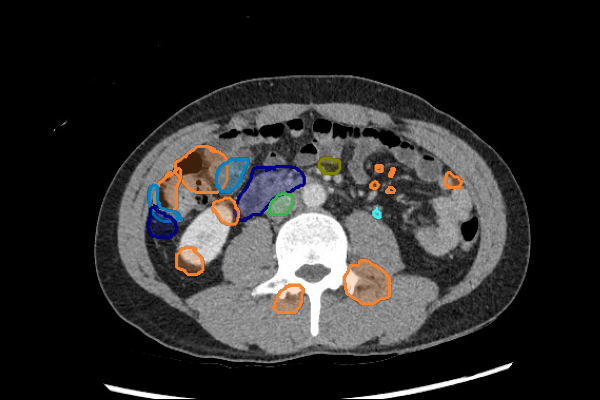

Legend

Slice 1

Slice 2

Slice 3

Slice 4

Slice 5

Slice 6

Slice 7

Slice 8

Slice 9

Slice 10

Slice 11

Slice 12